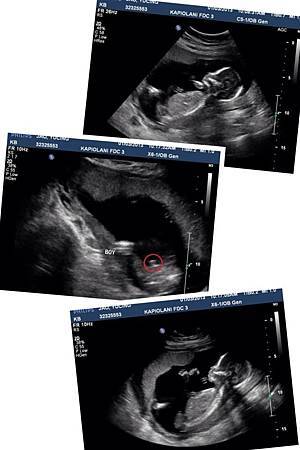

在18週的時候 DR. Tsai 又安排我照了一次超音波~

這次要看寶寶的性別喔! 還有做更詳細的高層次看看寶寶有沒有該發育的都有發育 等等

這次也一樣到 Kapiolani 婦幼醫院的超音波室做檢查